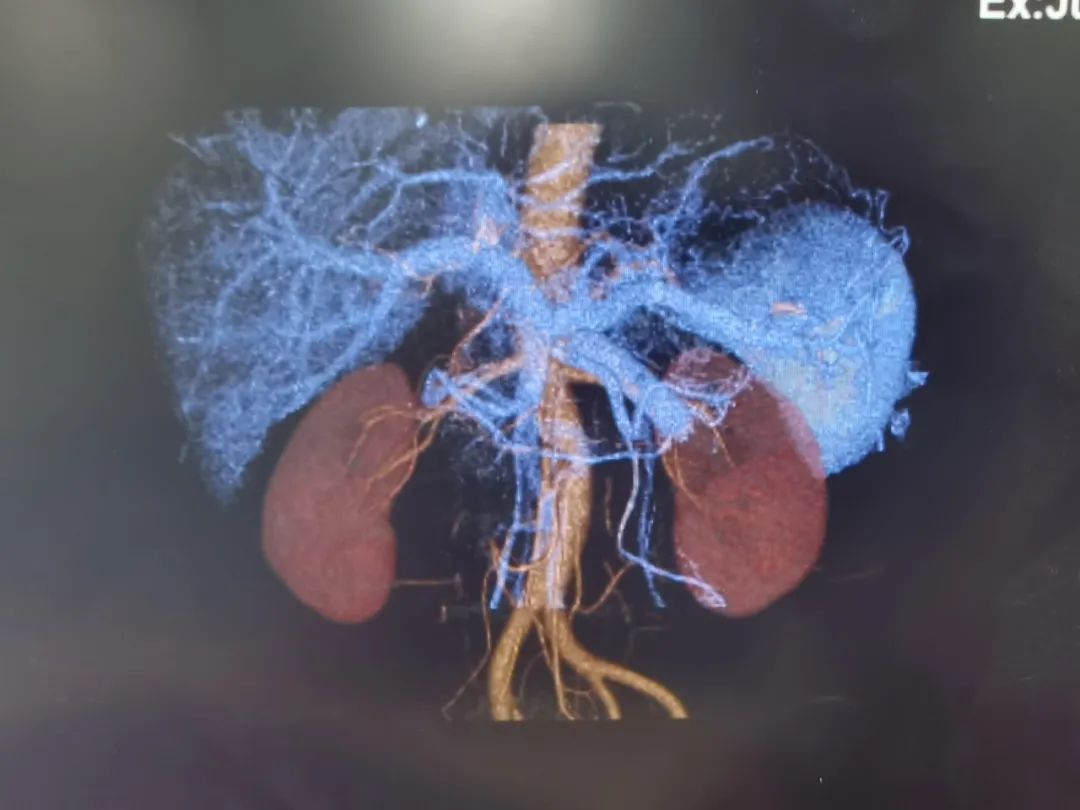

基于术前影像,结合肿瘤实际累及程度、解剖变异以及切离极限点,外科团队邀请多科室开展MDT讨论,规划个体化精准手术方案。充分术前准备后,为其行“肝门部胆管癌根治术”。主刀手沉着冷静,仔细探查,精准分离,清扫组织,以雷霆之势完整切除病灶。“清点器械纱布,确认无误,关腹。”手术顺利,经过术后严格管理和精心护理,宗师傅很快康复出院,对东方医院集团广济医院普外科团队精湛的技术赞不绝口。

“根治术手术切除被认为是肝门部胆管癌最佳治疗方式。”代坤主任解释道:肝门部胆管癌根治术被称为“肝胆外科手术的天花板”。需要精细的外科技术,是肝胆外科最具挑战性的技术领域。由于胆管的解剖结构特殊,肝门部胆管的肿瘤像长在大树干分叉甚至更高位置,胆管的主干在肝门部,但它的分叉在肝里面,想把这个位置的肿瘤切干净,需要对血管和胆管进行非常精细的解剖和保护,把胆管和血管分离到非常高的水平,尤其是保护好分叉非常细的血管,对肝功能恢复非常重要,有的可能需要联合肝叶切除。“宗师傅生病虽然不幸,但能够顺利进行肿瘤根治,对他的预后有着非常重要的意义,相信在我们医患共同的努力下,可以大大提高他的生活质量。”